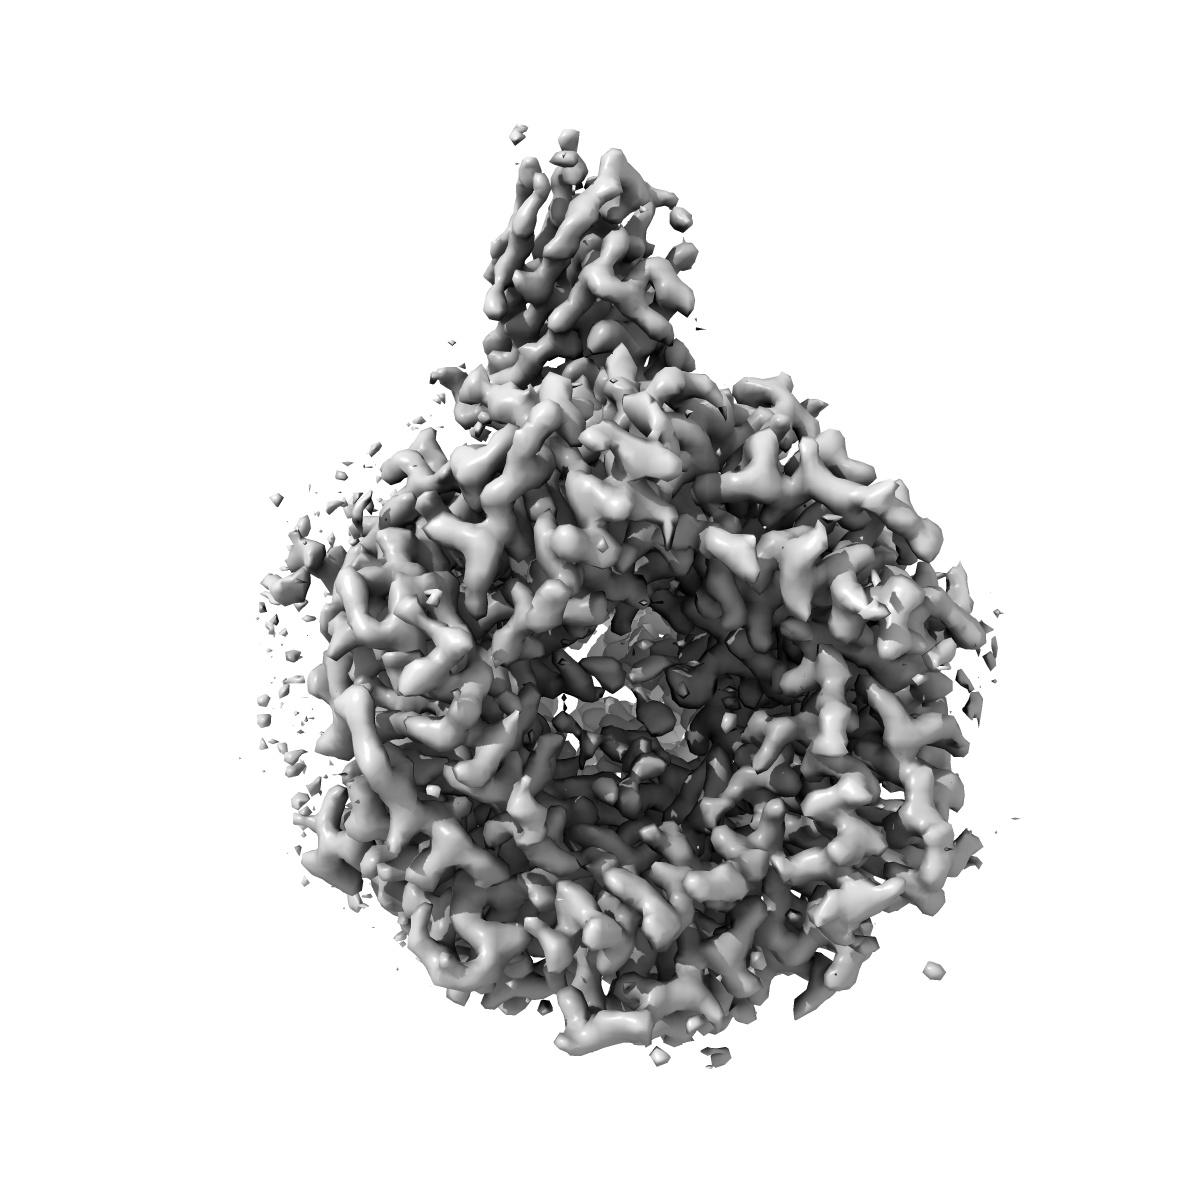

Cryo-EM structure of the human synaptic alpha1-beta3-gamma2 GABAA receptor in complex with Megabody38 in a lipid nanodisc

Sample: Human alpha1-beta3-gamma2 GABA-A receptor in complex with Megabody38 and in lipid nanodiscs

Fitted models: 6i53

Cryo-EM structure of the human alpha 1 beta 3 gamma 2 GABAAreceptor in a lipid bilayer.